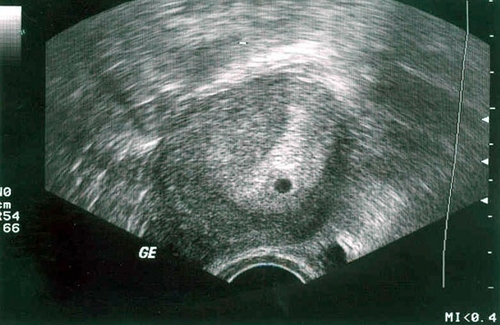

Si une femme se prépare à la conception et est théoriquement dans la deuxième semaine de grossesse (selon l'approche obstétricale), L'échographie aide à déterminer avec précision l'ovulation. Un médecin spécialiste confirmera que le follicule est prêt à libérer un ovule mature. Une telle étude est généralement menée chez des femmes ayant des problèmes de fertilité.

Dans la deuxième semaine après la conception, une échographie ne sera toujours pas informative. Il ne montrera que la disposition générale de l'utérus à supporter une grossesse. Si vous prenez une photo du scanner à ce moment, l'embryon ressemblera à un minuscule point noir.

Mais vous pouvez prendre un peu d'avance et vous rappeler comment certaines femmes pensent des semaines après un retard. Si deux semaines se sont écoulées depuis ce jour, la période obstétricale sera d'environ six semaines et la période fœtale sera de quatre. Et puis l'échographie enregistrera comment un petit cœur bat déjà.